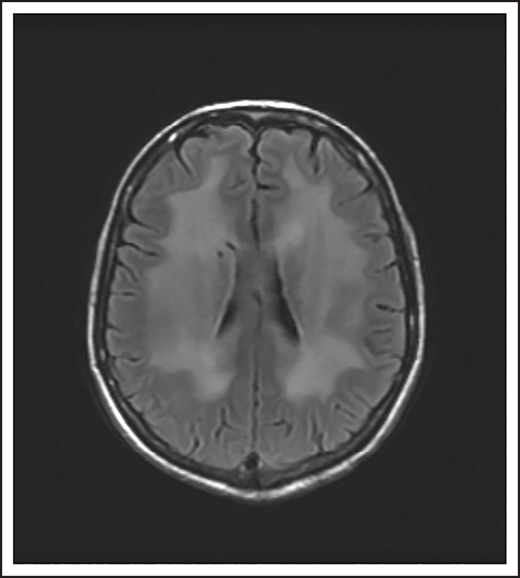

A 24-year-old man presented with stage IVB DLBCL and completed 6 cycles of R-CHOP, with FDG-PET after treatment showing resolution of all disease except in the mediastinum. After a biopsy of this residual FDG+-confirmed DLBCL, he received treatment with salvage chemotherapy with minimal response, followed by mediastinal involved field radiation therapy (IFRT) to a dose of 40 Gy plus a 6-Gy boost, after which he had a CR. Subsequently, he underwent autologous SCT followed by RIC allogeneic SCT. He remained in CR for 16 months, at which time he presented with 3 weeks of new right leg weakness, erectile dysfunction, and urinary hesitancy. The results of a brain MRI were unremarkable, but a spine MRI demonstrated spinal cord expansion and edema with multifocal enhancement within the prior radiation therapy portal from T5 to T9, demarcated by fatty marrow replacement between the T5 and T9 vertebral bodies (Figure 4). A diagnostic evaluation, including CSF analysis, was negative for malignancy, infection, autoimmune or inflammatory conditions, or demyelination. He was diagnosed with radiation-induced myelitis. He was treated with HD-MTX and had a minimal response. Treatment with bevacizumab led to complete resolution of the lesion, and after intensive physical therapy, he regained neurologic function.

MRI of the cervical and thoracic spine of a patient with radiation-induced myelopathy. (A) Axial T1-weighted image after gadolinium contrast shows enhancement within the spinal cord. (B) Sagittal T2 image shows a signal change throughout the patient’s prior radiation portal from T5 to T9, demarcated by fatty marrow replacement between the T5 and T9 vertebral bodies.

Radiation

Ionizing radiation to the brain or spinal cord can cause acute, subacute, or delayed adverse effects.58 Acute brain toxicity from radiation is typically related to cerebral edema and/or raised intracranial pressure and resolves with corticosteroids. Subacute effects caused by radiation-induced necrosis occur weeks to months after radiation and usually present with headache, lethargy, and focal neurologic deficits. Rarely, radiation myelopathy can result from focal radiation delivered to the mediastinum for HL and NHL, as in case 5.61 Spine MRI typically shows contrast enhancement within the spinal cord, and symptoms may resolve with corticosteroids. Bevacizumab has been used to treat radiation necrosis, as described in our case.62 Delayed neurotoxicity typically presents years after treatment. It can present as radiation-induced vasculopathy resulting in strokes or hemorrhage, or as brain atrophy and leukoencephalopathy. Older age and concurrent use of HD-MTX increase this risk.63